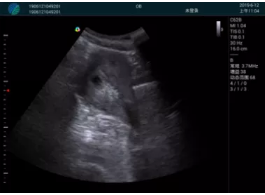

M20查看:囊內(nèi)回聲均勻,邊界清晰,囊壁光滑

M20引導抽吸術(shù)后囊腫消失,原區(qū)域空腔形成,脂肪層與腺體層架構(gòu)發(fā)生改變